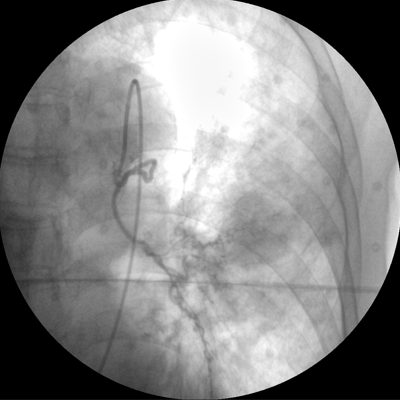

智能化控制系統(tǒng), 讓手術(shù)高效暢捷

專業(yè)的圖像處理系統(tǒng),為您提供高分辨率、高灰階圖像。